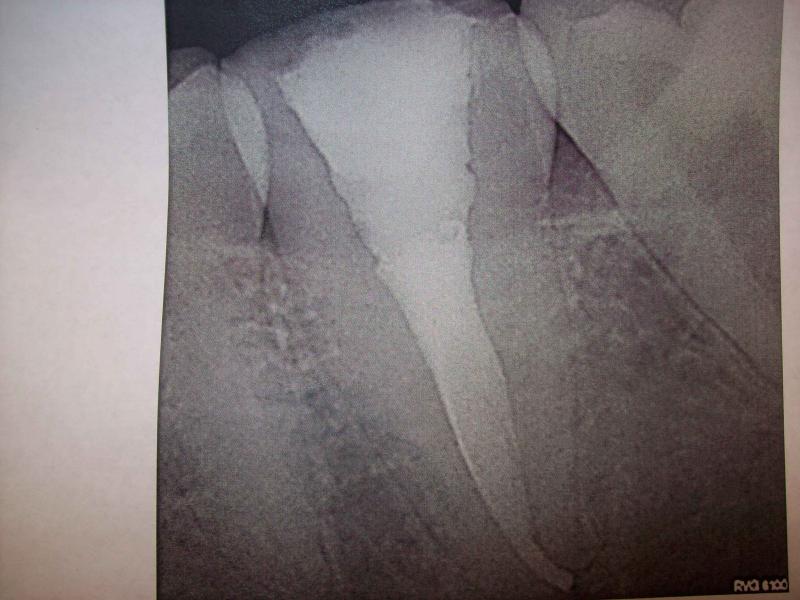

DR JET LOVES ROOT CANALS

General Dentist,  Performs Root Canals ONLY - Microscope Trained Dentist

"DR. JET'S MISSION IS TO PERFORM  ROOT CANALS FOR A REDUCED FEE USING THE LATEST TECHNOLOGY  AND TECHNIQUES TO SERVICE THE MANY PEOPLE WHO ARE UNINSURED OR UNDER-INSURED GIVING EVERYONE AN OPPORTUNITY TO SAVE THEIR TOOTH!"

**PLEASE BE AWARE THAT  A ROOT CANAL IS AN ATTEMPT TO SAVE YOUR ALREADY DAMAGED TOOTH.  THERE IS NO GUARANTEE THAT ANY TOOTH CAN BE SAVED BUT DR JET WILL DO HIS BEST TO HELP YOU. THE OTHER OPTION IS TO EXTRACT YOUR TOOTH